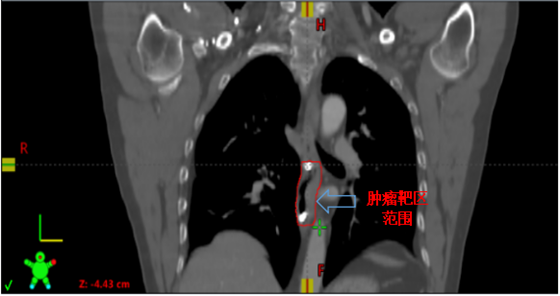

金属钛夹标记病变部位

接诊后,肿瘤科钟美佐主任同李军烽副主任医师结合患者既往病史和实际情况决定对病变部位实施放射治疗。考虑到患者食管病变较早,CT无法清晰显示病变部位及范围,患者曾经又接受过上段食管放射治疗,为进一步减少照射范围,准确定位肿瘤位置,肿瘤科联合消化内科,通过消化内镜在原位癌处附近植入金属钛夹标记物后再行增强CT,根据钛夹位置对病灶实施精准定位,尽可能的减少不必要的照射,降低患者放疗副作用的发生。目前高大哥已结束放射治疗,不适症状得到明显缓解。